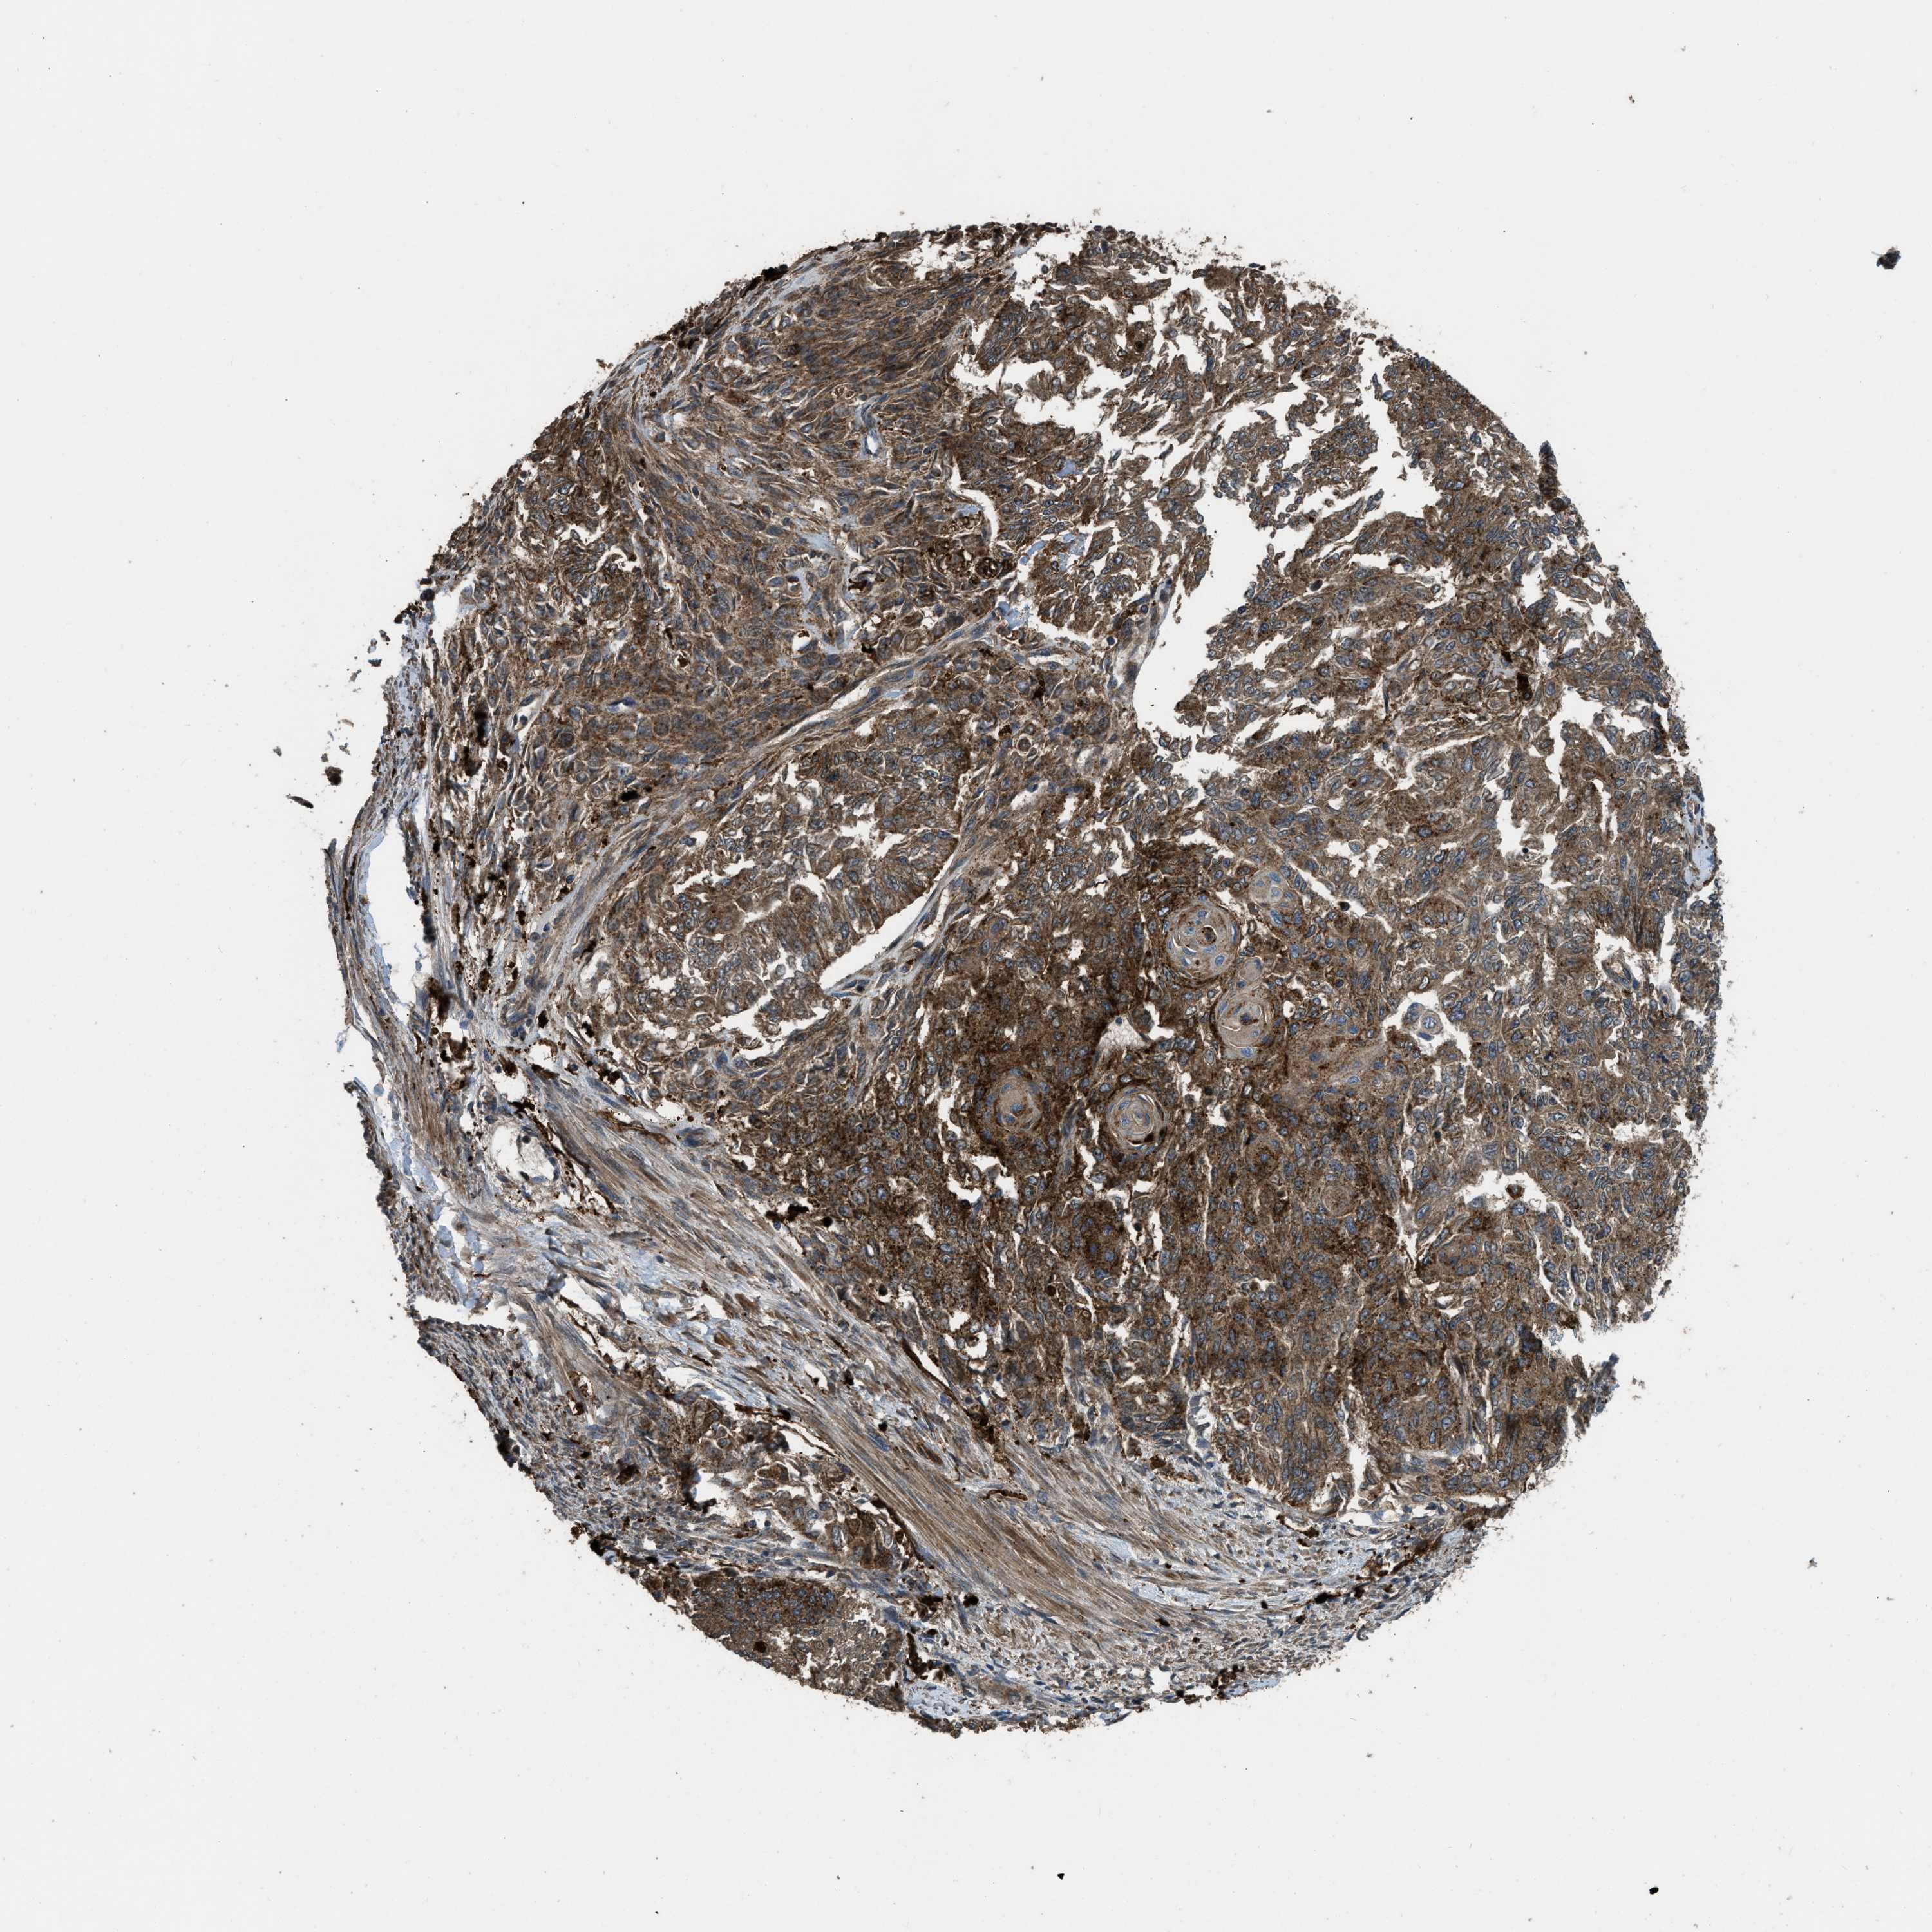

ENDOMETRIAL CANCER - Protein expressioni

A mouse-over function shows sample information and annotation data. Click on an image to view it in a full screen mode. Samples can be filtered based on level of antibody staining by selecting one or several of the following categories: high, medium, low and not detected. The assay and annotation is described here.

Note that samples used for immunohistochemistry by the Human Protein Atlas do not correspond to samples in the TCGA dataset.

Antibody stainingi

Antibody staining in the annotated cell types in the current human tissue is reported as not detected, low, medium, or high, based on conventional immunohistochemistry profiling in selected tissues. This score is based on the combination of the staining intensity and fraction of stained cells.

Each image is clickable and will lead to virtual microscopy that enables deeper exploration of all samples and also displays staining intensity scores, fraction scores and subcellular localization as well as patient and tissue information for each sample.

Antibody HPA025226

Antibody CAB019296

Staining

High

Medium

Low

Not detected

Intensity

Strong

Moderate

Weak

Negative

Quantity

>75%

75%-25%

<25%

None

Location

Nuclear

Cytoplasmic/membranous

Cytoplasmic/membranous,nuclear

Adenocarcinoma, NOS

Adenocarcinoma, metastatic, NOS